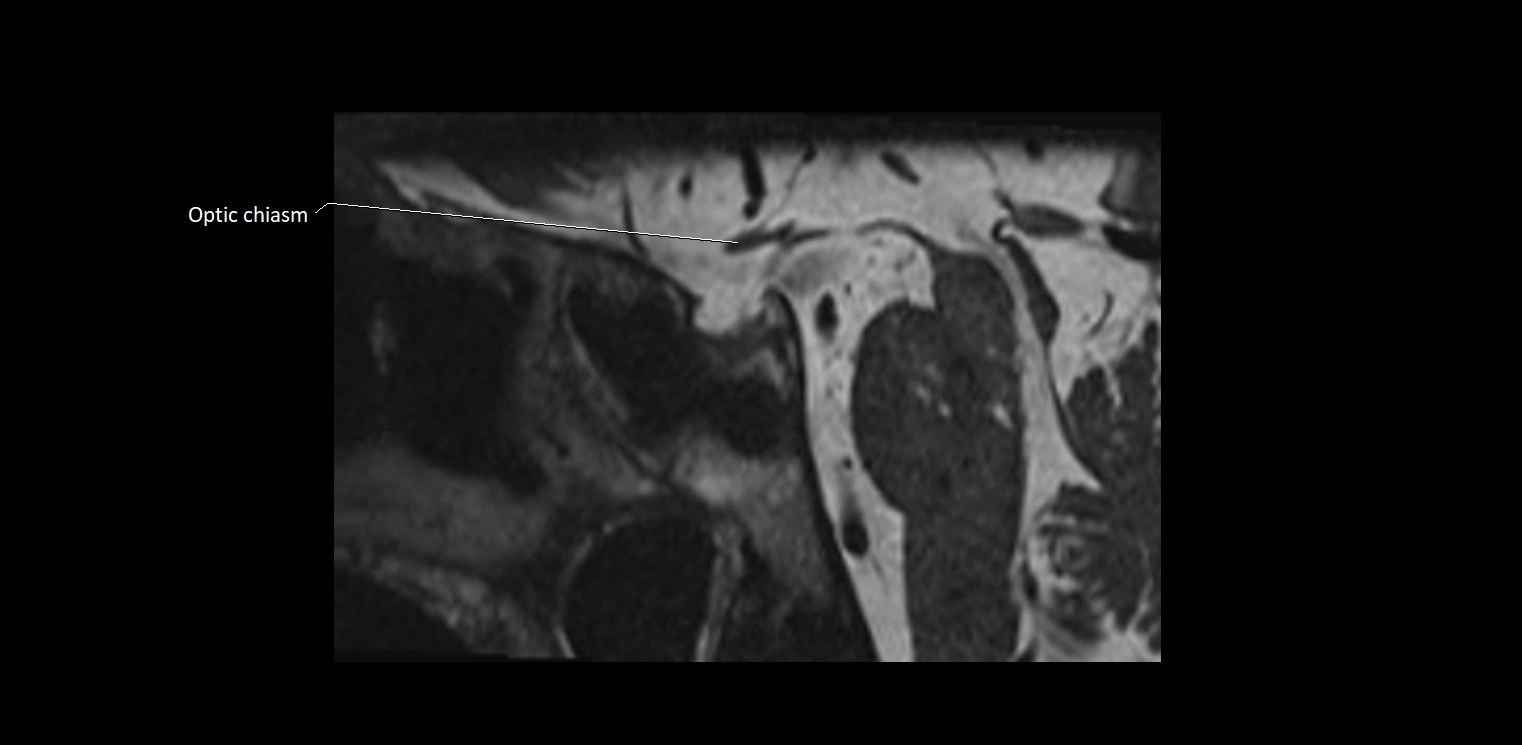

MRI Appearance

• The abducens nerve is a small, thin, linear structure

• Best visualized on high-resolution T2-weighted 3D MRI sequences (e.g., FIESTA or CISS)

• Seen as a hypointense (dark) line running from the brainstem at the pontomedullary junction, traversing the prepontine cistern, and entering Dorello’s canal under the petrosphenoidal ligament, then into the cavernous sinus, and finally the orbit

• May be challenging to visualize in standard MRI due to its small size

• Pathology may be inferred by absence, displacement, or enhancement of the nerve